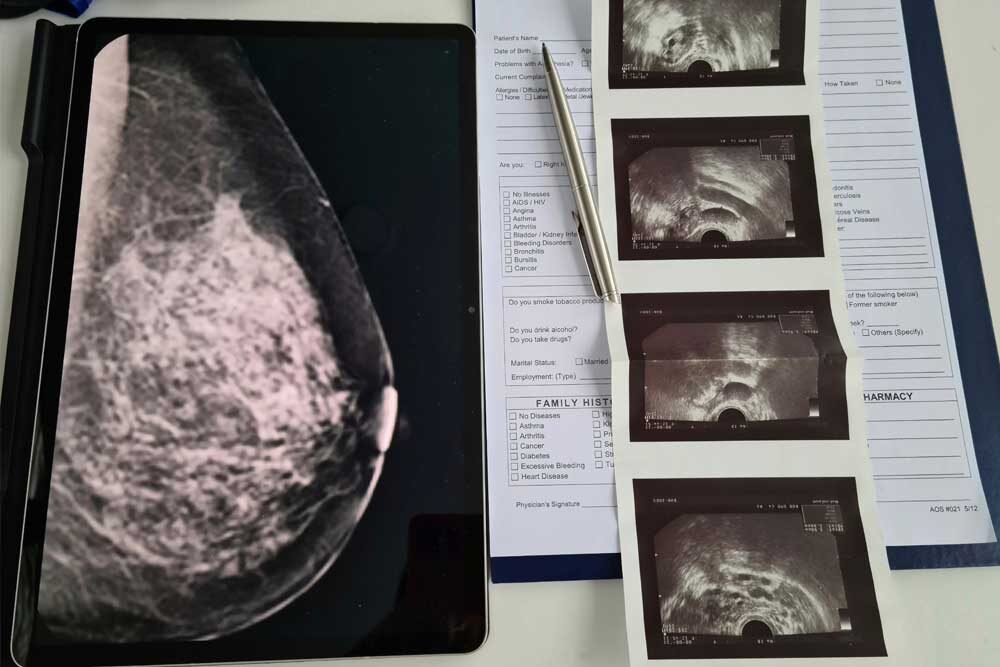

Ultrasound and MRI as Diagnostic Tools

Breast ultrasounds can distinguish between solid masses and fluid-filled cysts, using sound waves rather than radiation to generate detailed images. For women with dense breast tissue or those at high risk, breast MRIs offer a more nuanced view, helping to differentiate normal tissue from abnormalities.